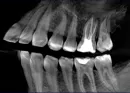

Два с половиной месяца назад появилась сильная чувствительность к холодному, горячему в депульпированный 6-ке сверху слева (зуб был депульпирован 5 лет назад, беспокойства никогда не причинял). Также зуб реагирует легкой болью на надавливание. В процессе еды чувствуется только первый надкус на этот зуб, дальше все нормально. Соседние зубы полностью здоровы, что подтверждает стоматолог. Есть КТ верхней челюсти.

Один из корней зуба пройден не до верхушки и имеет воспаление в области апекса. Необходимо наблюдать за зубом в динамике по снимкам. Возможно, это на фоне предшествующего патологического процесса остаточные симптомы.